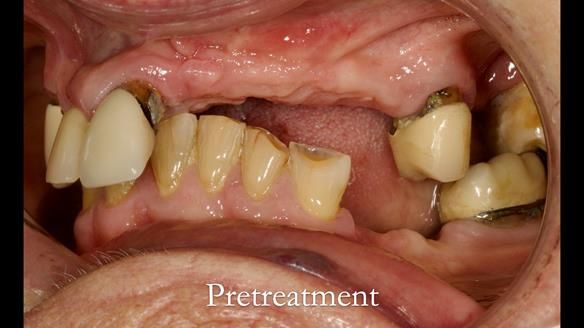

Aesthetically and functionally poor RPDs were replaced for Eileen, a 74 year old woman.

Referred to me by her general dental practitioner specifically for replacement RPDs.

Dental concerns

“Top denture loose making conversation difficult at times. Also, appearance isn’t good. Teeth uneven”

Diagnoses

- Missing teeth in the upper and lower jaws

- Upper and lower metal based RPDs, poorly fitting, worn occlusal surface, reverse curve aesthetics, lacking support

- Poor dental appearance with reverse incisal curve

- The upper right central and lateral incisors with post crowns. Healthy and functionally secure but with poor appearance, contributing to the reverse curve.

- Moderate to heavily restored dentition with deep overbite (Class 2 div II)

- Yellowish lower front teeth with small amount of wear.

- The lower right canine (LR3) is worn with MOD cavity.